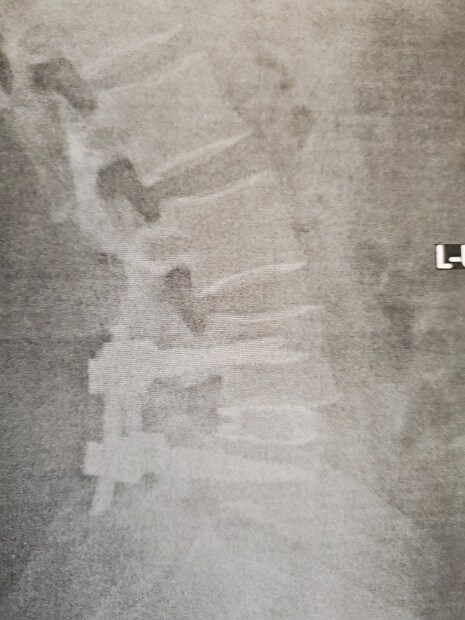

I went and saw the doctor yesterday, the fusion is taking well the recovery is going good, my L4 and L5 went from being about 35% out of alignment to back to alignment, the doctor was afraid that he might not be able to get it back to less than 15% due to how bat it was, but look at those sexy vertebrates now.

Post Image